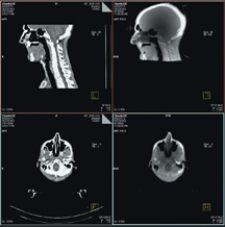

MVision, from Siemens Medical Solutions, is a volumetric inline target imaging solution and the natural next step in Image-Guided Radiation Therapy (IGRT). Designed to work with Siemens’ linear accelerators, the system is the first commercial implementation of cone-beam technology utilizing a standard radiotherapy treatment beam. MVision makes it possible for the megavoltage (MV) source used for treatment to also create a 3-D image of the patient, enabling clinicians to “see inside” the patient at the most appropriate moment.

MVision fully integrates and automates all processes, including acquisition, reconstruction, registration, assessment, patient positioning and clinical review. With a few steps, therapists can calculate 3-D offsets, send them to the treatment couch to compensate for daily variations and safely deliver therapy.